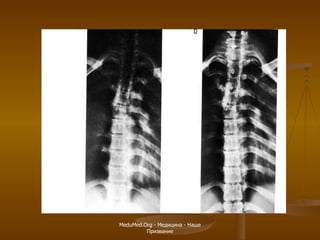

МРТ шейного отдела позвоночника Продолговатый мозг Спинной мозг Второй шейный позвонок Межпозвонковый диск Тело пятого позвонка Остистый отросток Мозжечок Первый шейный позвонок

MeduMed.Org -  Медицина - Наше Призвание

МРТ пояснично-крестцового отдела позвоночника Крестец Пятый поясничный позвонок Межпозвонковый диск (пульпозное ядро) Спинной мозг Конский хвост Копчик Остистый отросток Межпозвонковый диск (фиброзное кольцо)

МРТ пояснично-крестцового отдела позвоночника Миелография Аксиальная плоскость Позвоночный канал Остистый отросток Фасеточный сустав Межпозвонковый диск Позвоночный канал Конский хвост